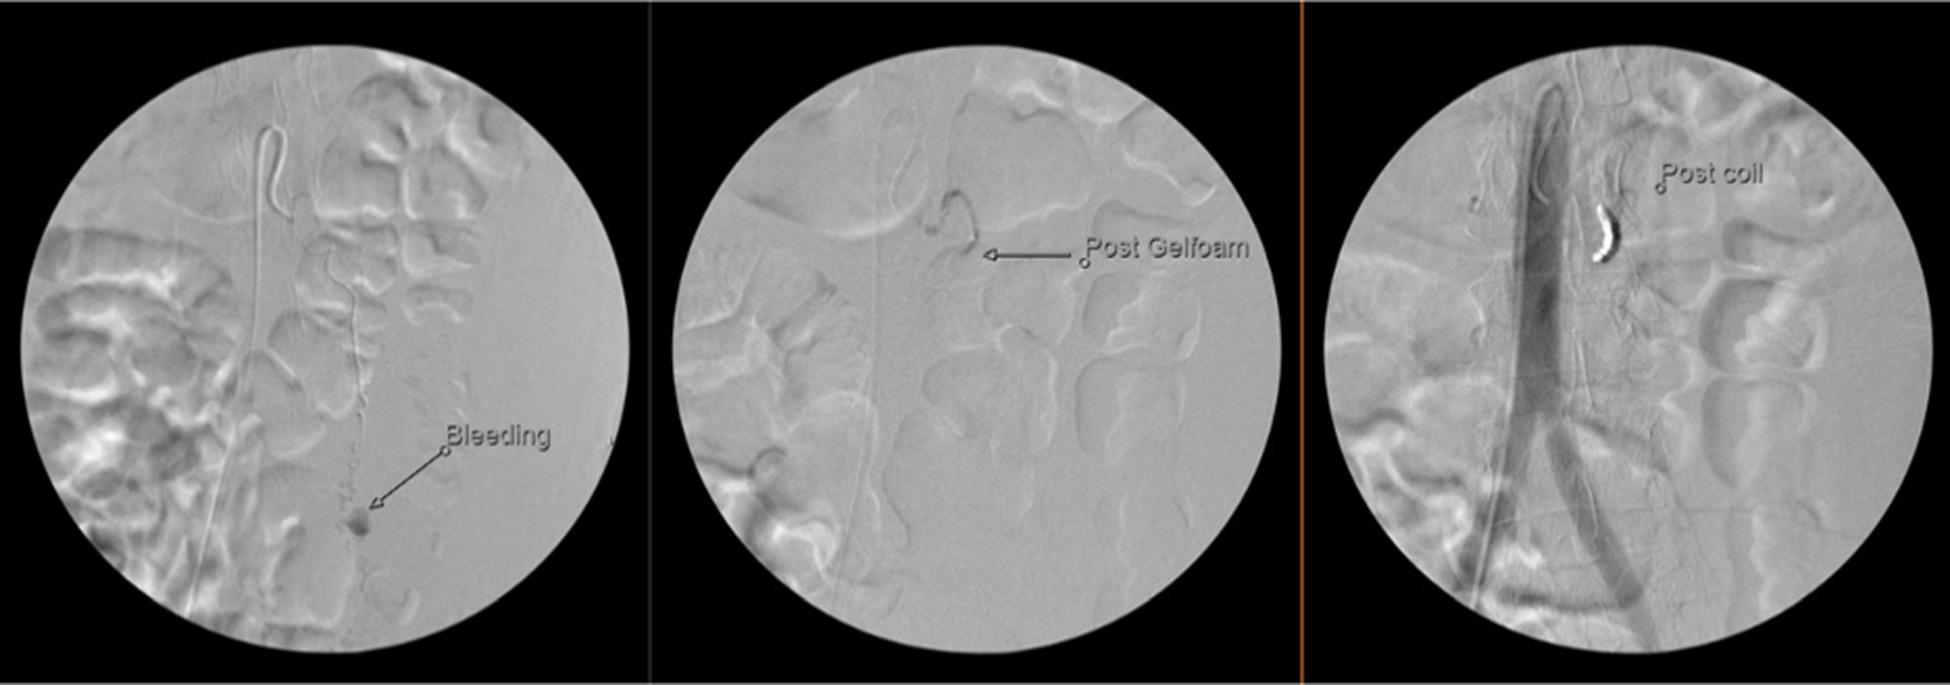

143 Ruptured Ovarian Artery Aneurysm in a Postmenopausal Female: Case Report

Raj Patel, Amy Russell, Melanie M. Randall